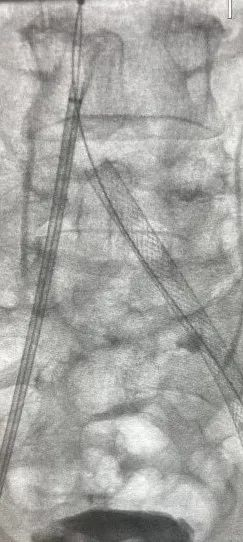

手术过程:

患者取仰卧位,在局部麻醉下通过左侧足背静脉顺行造影,结果显示左侧髂股静脉血栓负荷较重。随后,经右侧股静脉入路,成功置入血栓保护装置于下腔静脉预期位置,确保术中脱落的血栓能够被有效拦截。之后,再经左侧腘静脉入路,对髂股静脉狭窄区域依次进行血栓清除术和球囊扩张术,并成功植入髂静脉支架。术后造影显示,左侧髂股静脉血流恢复通畅,同时血栓保护装置内见少量血栓充盈缺损,随后经右侧股静脉负载血栓回收血栓保护装置,并将其撤出体外,取出后可见拦截到的不同尺寸的血栓,手术顺利完成。

造影髂股静脉

有较多血栓

术中血栓保护

(血栓抽吸过程)

(支架植入过程)